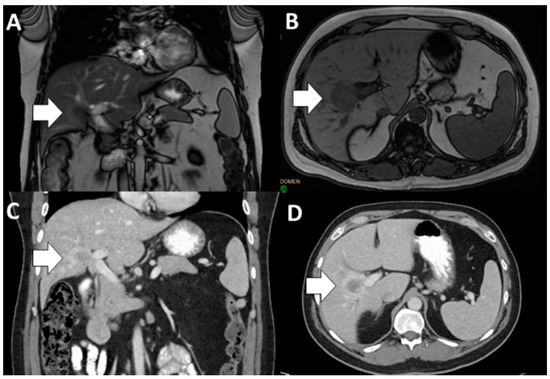

- Fábrega-Foster, K.; Ghasabeh, M.A.; Pawlik, T.M.; Kamel, I.R. Multimodality imaging of intrahepatic cholangiocarcinoma. HepatoBiliary Surg. Nutr. 2017, 6, 67–78. [Google Scholar] [CrossRef] [PubMed]

- Seo, N.; Kim, D.Y.; Choi, J.Y. Cross-sectional imaging of intrahepatic cholangiocarcinoma: Development, growth, spread, and prognosis. Am. J. Roentgenol. 2017, 209, W64–W75. [Google Scholar] [CrossRef]

- Itai, Y.; Ohtomo, K.; Kokubo, T.; Yamauchi, T.; Minami, M.; Yashiro, N.; Araki, T. CT of Hepatic Masses: Significance of Prolonged and Delayed Enhancement. Am. J. Roentgenol. 1986, 400, 729–733. [Google Scholar] [CrossRef]

- Kim, R.; Lee, J.M.; Shin, C.I.; Lee, E.S.; Yoon, J.H.; Joo, I.; Kim, S.H.; Hwang, I.; Han, J.K.; Choi, B.I. Differentiation of intrahepatic mass-forming cholangiocarcinoma from hepatocellular carcinoma on gadoxetic acid-enhanced liver MR imaging. Eur. Radiol. 2016, 26, 1808–1817. [Google Scholar] [CrossRef]

- Fowler, K.J.; Saad, N.E.; Linehan, D. Imaging approach to hepatocellular carcinoma, cholangiocarcinoma, and metastatic colorectal cancer. Surg. Oncol. Clin. N. Am. 2015, 24, 19–40. [Google Scholar] [CrossRef]